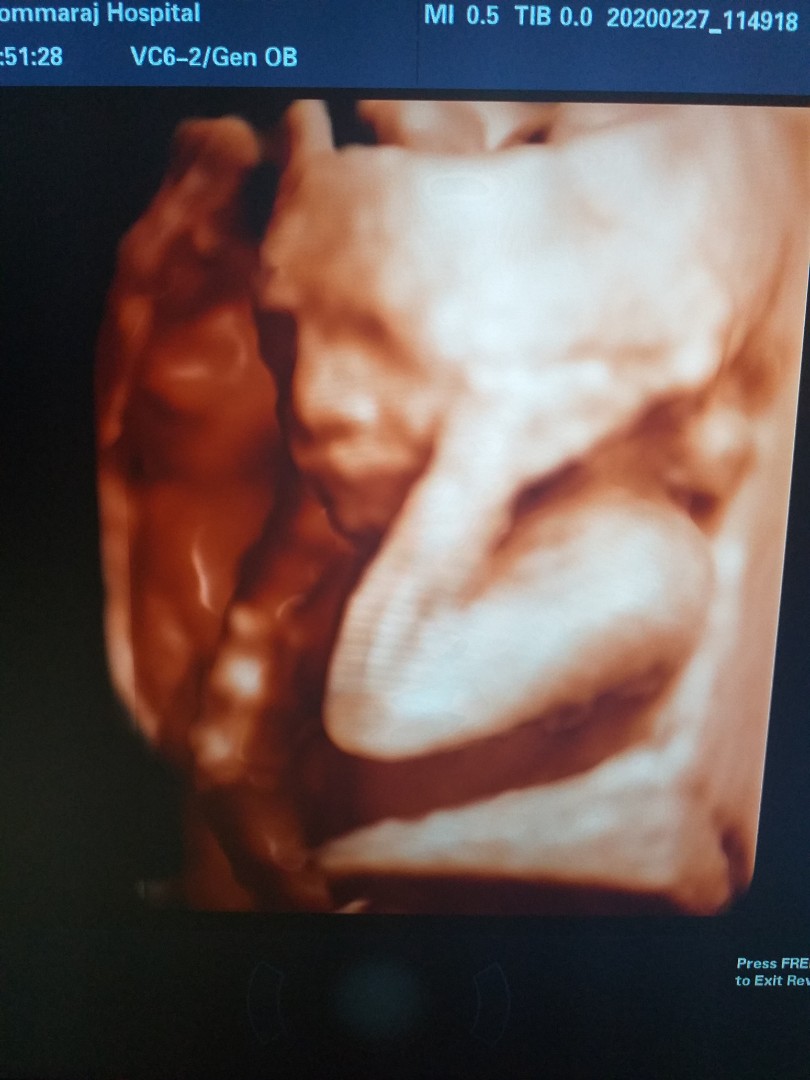

ลูกสาวค่ะ ซาวตอน24w